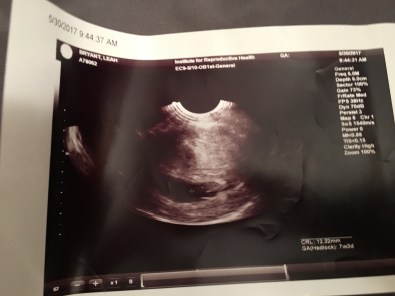

Our first ultrasound took place on May 30th, in the morning. At this time I was 7 weeks and still in that fog of – is this real? – is this happening?

At first, neither one of us had an idea of what we were looking at. That’s when he put the mouse at one end and then the other end of our little one. Yes, just one – we are completely stoked about that! With the infertility drugs and me being over 35, there was a possibility of twins. Which would have been completely fine too!

Then from a different angle he was showing us, we could see the heart beating away! That’s when for whatever reason, I decided to reach out and touch the screen. Probably that goober side taking over again. haha

The doctor said that all looked as should and to come back in two weeks. He then picked up his little spin wheel to tell us our due date. (I had already googled this and knew it was around January 13/14th, but it’s always nice to have the official due date from the doctor!)

Our due date is January 13th, 2018! Mark your calendars for our little miracle to arrive! WOOHOO

So here we are, waiting for another 2 weeks to pass by for another visit. Until then, you can admire our copy of the pictures 🙂